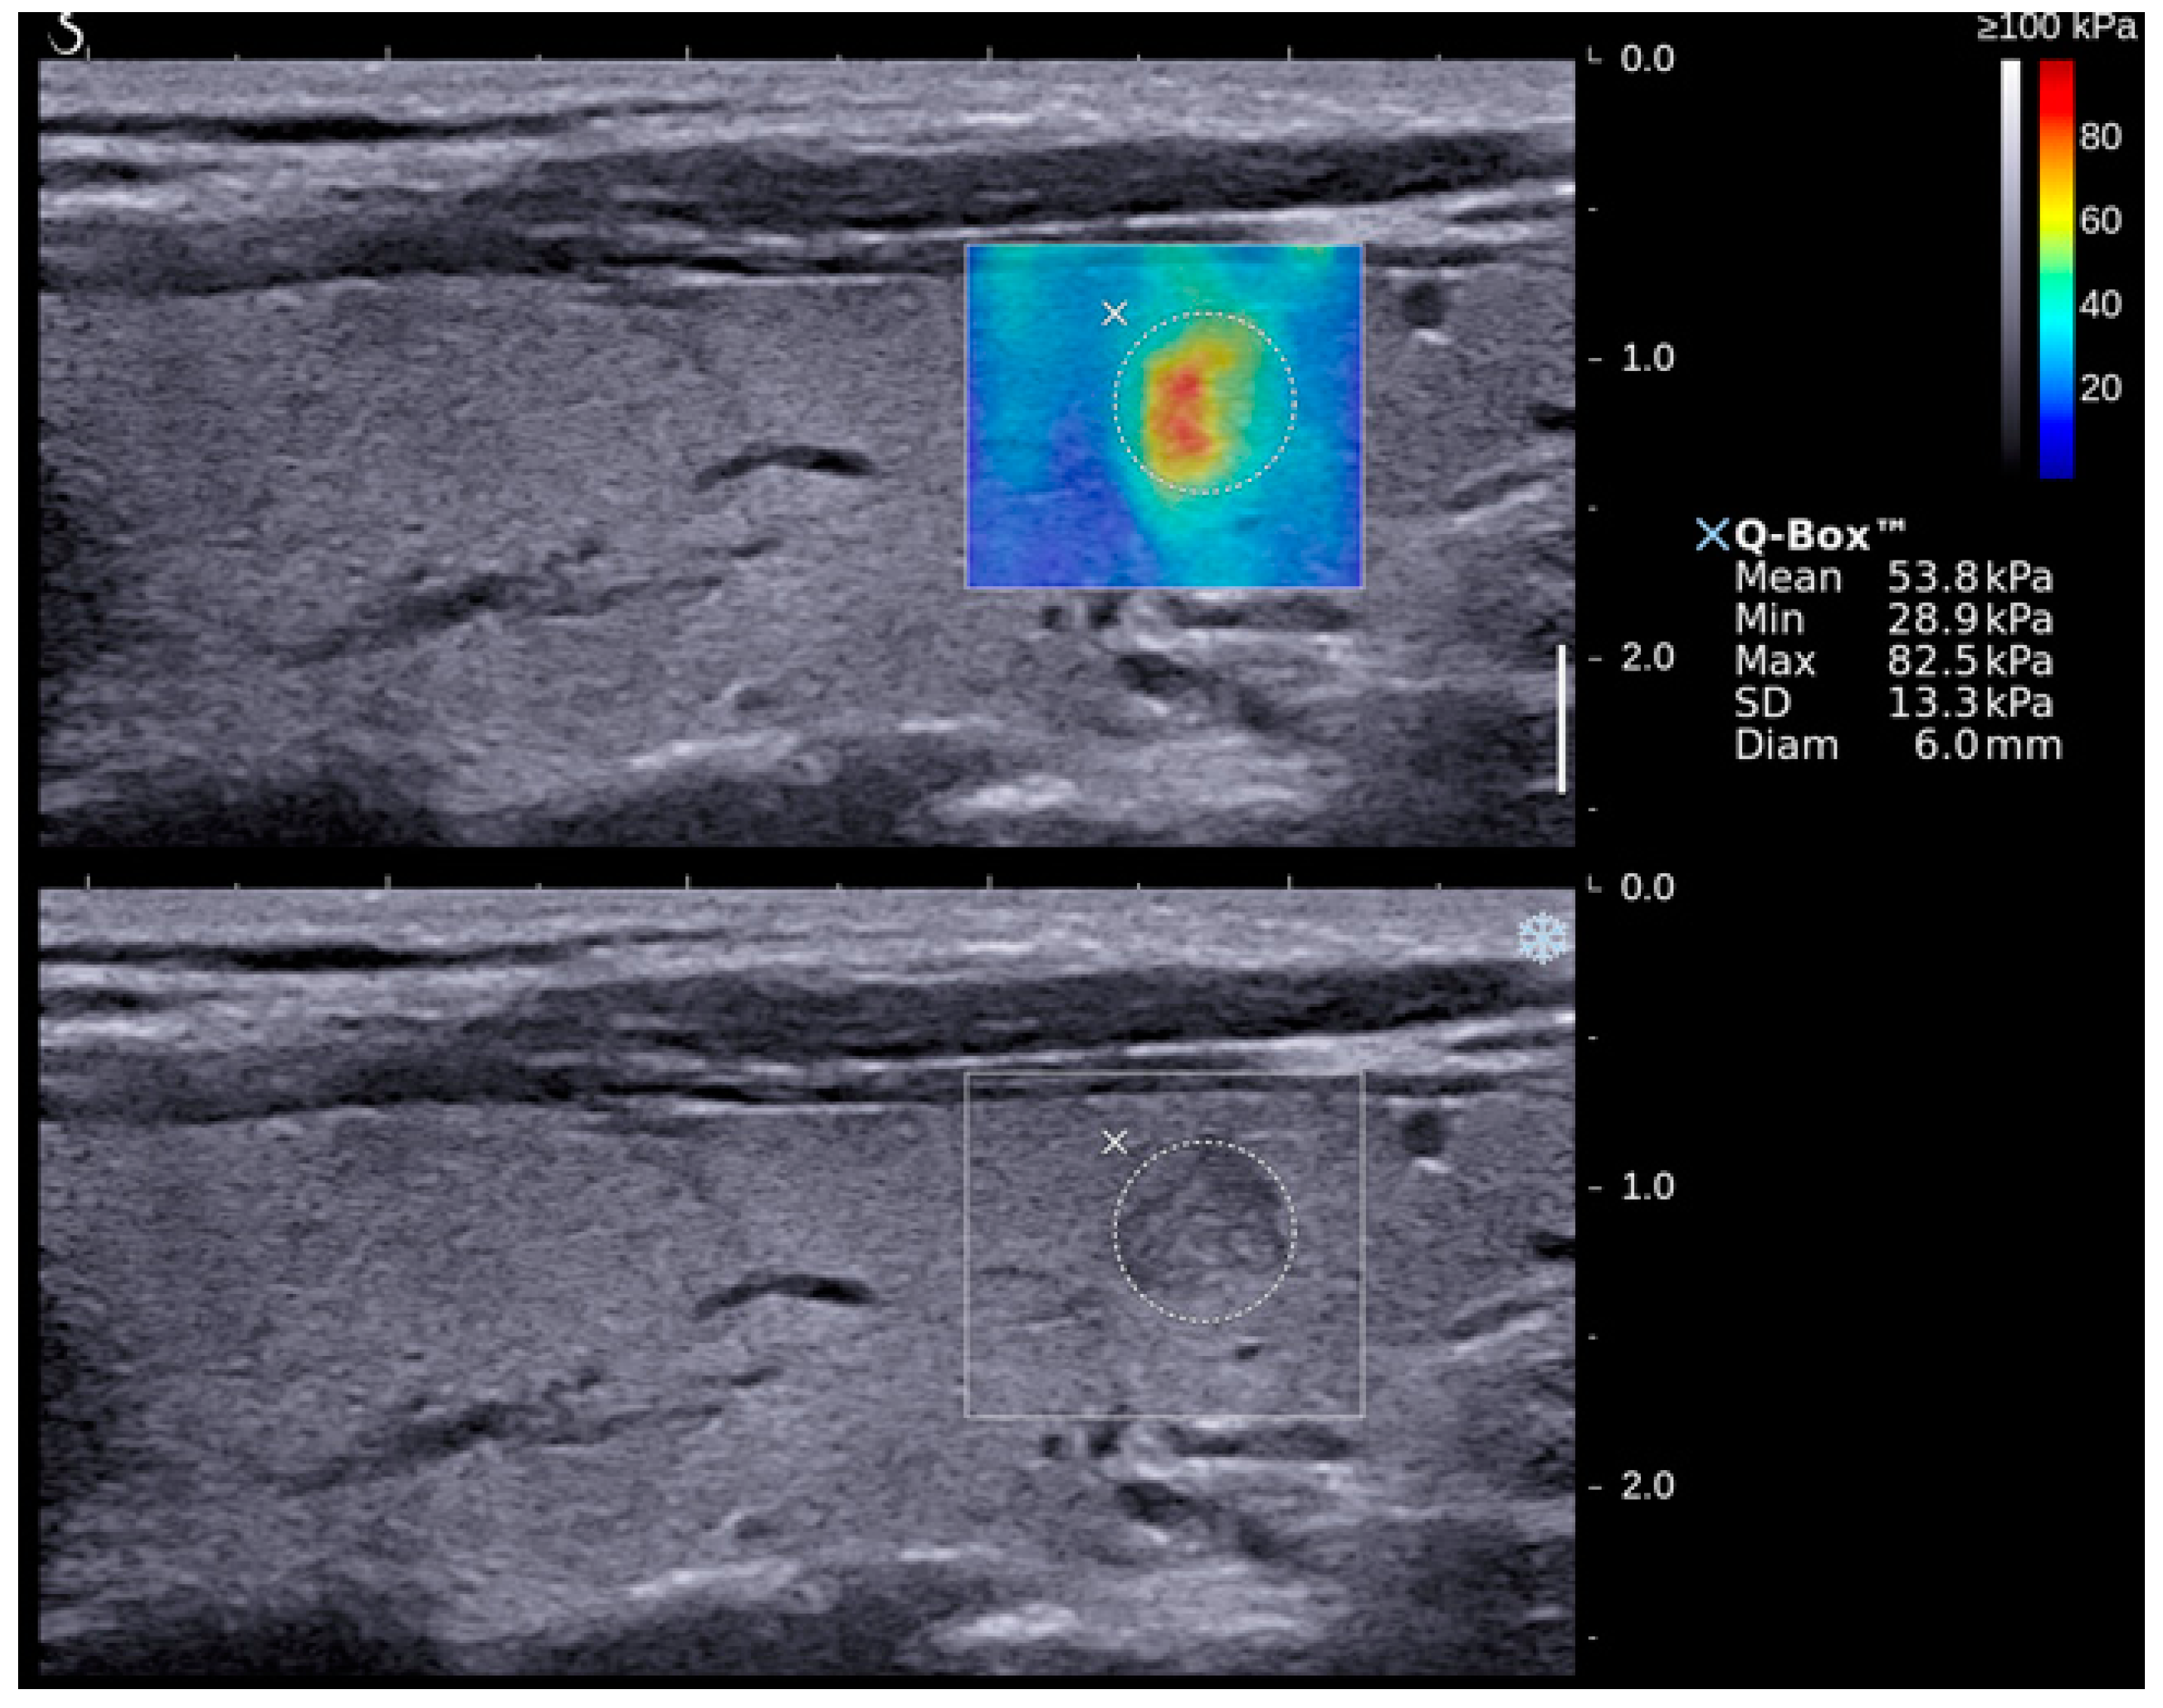

| Emax | 50.3 ± 3.1 | 85.2 ± 8.1 | <0.05 (50.9–63.5; 73.0–106.1) |

| Emean | 20.2 ± 1.0 | 26.6 ± 2.5 | <0.05 (19.5–23.5; 23.5–33.9) |